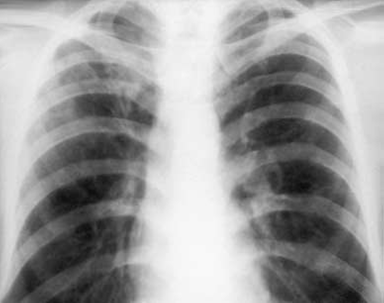

Рис. 1. Больной Ш., 19 лет. Обзорная рентгенограмма. Очаговый туберкулез. Справа в подключичной зоне на фоне фиброзных изменений определяются множественные очаги средней плотности Очаговый туберкулез может быть как самостоятельной формой, так и вариантом заживления других клинических форм легочного туберкулеза. Практически любая форма легочного туберкулеза в процессе заживления, инволюции может трансформироваться в очаговые изменения. В большинстве случаев при очаговом туберкулезе экссудативная тканевая реакция довольно быстро сменяется продуктивной. Поэтому в пораженном участке удается видеть наряду с ацинозной и лобулярной бронхопневмонией формирование продуктивных бугорков – как одиночных, так и сливающихся в более крупные ацинознодозные образования. В рентгенологическом изображении свежие очаги имеют сравнительно небольшие размеры (1–1,5 см), округлую, овоидную, грушевидную или розеткообразную форму, низкую интенсивность, однородную структуру, более или менее четкие контуры. Размеры очагов, как правило, не превышают размеров дольки легкого. Мелкие очаги диаметром 3–4 мм чаще имеют продуктивно-фиброзный характер, крупные очаги отражают экссудативно-казеозный тип реакции. Изменения локализуются преимущественно в верхушечно-задних сегментах легких. В зависимости от морфологической картины выделяют несколько вариантов очагового туберкулеза легких: - острый очаговый туберкулез легких; - фиброзно-казеозные очаги в стадии обострения или без признаков активности; - очаги и рубцы на месте заживших каверн. Свежие туберкулезные очаги, или острый очаговый туберкулёз, по определению А.И. Струкова (1948), морфологически характеризуется наличием не больших фокусов казеозной пневмонии, занимающих дольку легкого или часть ее. Подобный очаг впервые был описан А.И. Абрикосовым (1904) и расценен им как реинфект, возникший в результате повторного заражения аэрогенным путем. Однако позднее было доказано, что эти очаги не имеют отношения к аэрогенной суперинфекции, а возникают в результате обострения специфического воспаления вокруг мелких и мельчайших очажков. Сам А.И. Абрикосов видел мелкие старые очажки, располагающиеся в зоне свежего воспаления, но не придал им значения с точки зрения генеза вторичного туберкулеза и образования свежего воспалительного фокуса с казеозным некрозом. Рентгенологическая картина при этом варианте очагового туберкулеза довольно характерна: 1. Обычно определяется несколько очагов, располагающихся в 1 или 2 сегменте, иногда обнаруживают два или один очаг. 2. Интенсивность тени небольшая. 3. Контуры могут быть нечеткими или относительно четкими. 4. Форма очагов округлая или овальная. 5. Размеры свежих туберкулезных очагов могут значительно уменьшаться за счет рассасывания перифокальной инфильтрации, частичной резорбции казеоза и деструкции. 6. Если очаг кавернизируется, то каверна имеет тонкие стенки, и в течение 3 – 4 мес. на ее месте формируется очажок размерами 2 – 3 мм. В тех случаях когда кавернизации не происходит, краевой распад виден на структурных томограммах при размере деструкции не менее 4 мм. Фиброзно-казеозные очаги представляют собой фокусы инкапсулированного казеозного некроза размером до 1 см. В некоторых из них обнаруживают отложения солей кальция. Фиброзно-казеозные очаги могут находиться в двух состояниях: – в фазе стабилизации процесса; – в фазе обострения. В зависимости от этого наблюдаются различные рентгенологические симптомы. В стадии стабилизации процесса , или в фазе уплотнения и кальцинации, на фоне неизмененной легочной ткани определяется несколько очагов с довольно четкими контурами, вкраплениями кальция или полным обызвествлением. Плевра над верхушками легких иногда незначительно утолщена. Легочный рисунок в пределах пораженных сегментов не изменен. Вокруг очагов, особенно если они располагаются группами, могут быть радиарно расходящиеся рубцовые линейные тени. При обострении процесса появляются все признаки воспаления: нечеткость контуров очагов за счет перифокальной зоны инфильтрации, воспалительный ограниченный лимфангит как следствие распространения процесса по перибронхиальным и периваскулярным пространствам с формированием мелких и более крупных свежих очагов, краевая деструкция. Все эти изменения более отчетливо определяются на структурных томограммах.